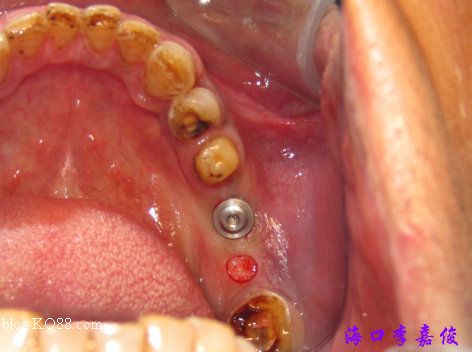

36種植窩成形后要植入4.8X13mm植體

下牙牙齦菲薄

37種植窩成形后植入4.8X10mm植體

術(shù)后